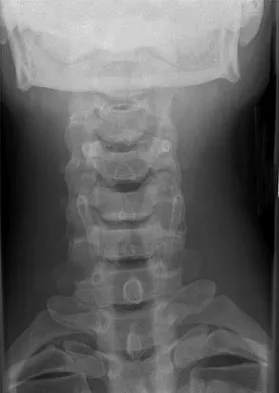

Figure 7 shows the radiograph of a 64-year-old man who has neck pain and weakness of the upper and lower extremities following a motor vehicle accident. Examination reveals 3/5 quadriceps and 4/5 hip flexors but no ankle dorsiflexion or plantar flexion. His intrinsics are 1/5, with finger flexors of 3/5. He is awake, alert, and cooperative. Management should consist of

Explanation

In patients with facet dislocations and an incomplete neurologic deficit, early decompression of the canal via reduction of the dislocation generally is considered safe if the patient is alert and can cooperate. However, patients who cannot cooperate with serial neurologic examinations during the reduction are at risk for increased deficit secondary to herniated nucleus pulposus, and MRI should be performed prior to either closed or open reduction. Star AM, Jones AA, Cotler JM, et al: Immediate closed reduction of cervical spine dislocations using traction. Spine 1990;15:1068-1072.